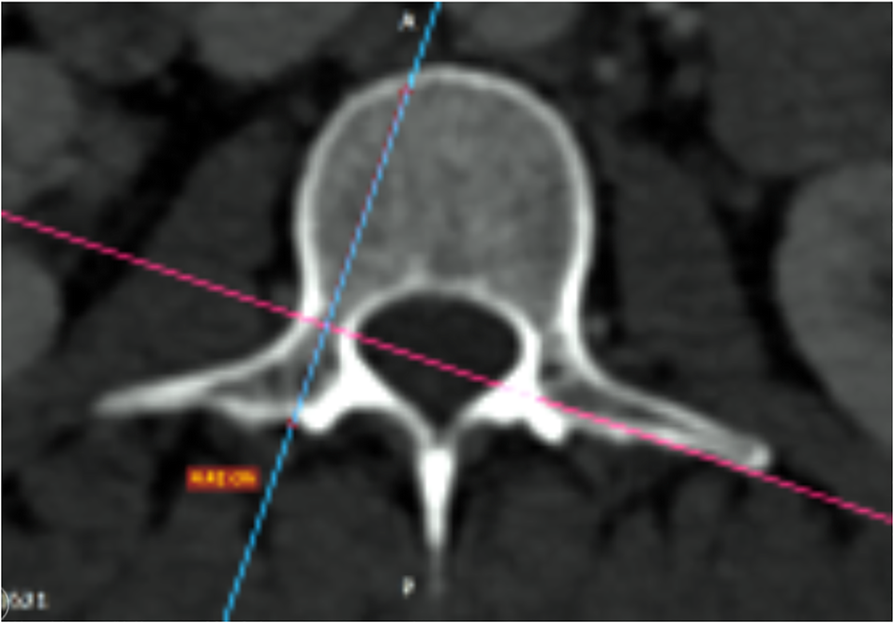

Fig. 5

The postero-anterior trajectory’s length of the pedicle from the entry point of a hypothetical screw to the anterior cortex of the vertebra (PTLP) for the right- and left-sided pedicles